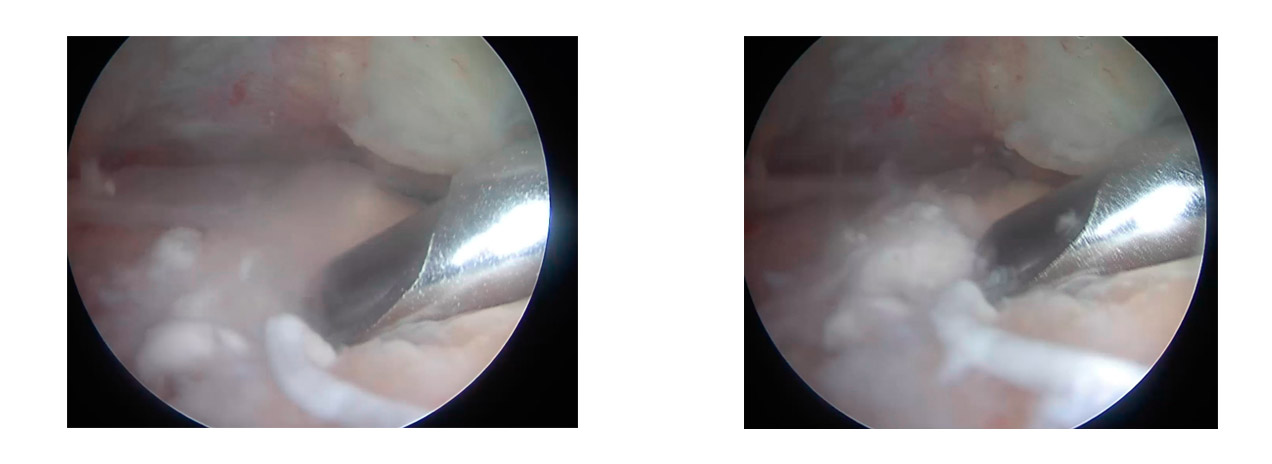

Artroskopik debridman, bir ameliyathanede, genel anestezi altında yapılan minimal invaziv bir cerrahi işlemdir.

- İşlem: Omuza açılan 2-3 küçük kesi (delik) aracılığıyla bir kamera (artroskop) yerleştirilir. Bu kamera sayesinde cerrah, omuz ekleminin ve tendonların içini ekrandan net bir şekilde görür. Ardından, diğer kesilerden sokulan özel cerrahi aletlerle kalsiyum birikimleri temizlenir.

- Ne zaman tercih edilir? Cerrahi genellikle şu durumlarda önerilir:

- Kalsifikasyona eşlik eden tendon yırtığı varsa,

- Kalsiyum birikimi çok yoğun ve yaygınsa,

- Barbotaj gibi ameliyatsız yöntemlerle yeterli sonuç alınamamışsa.